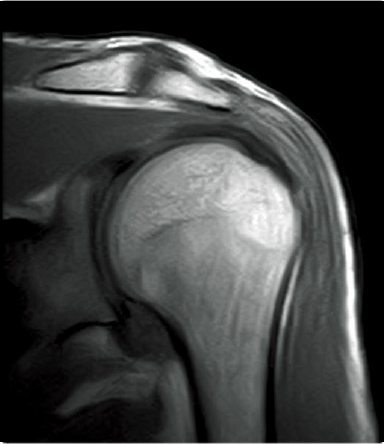

T2WI